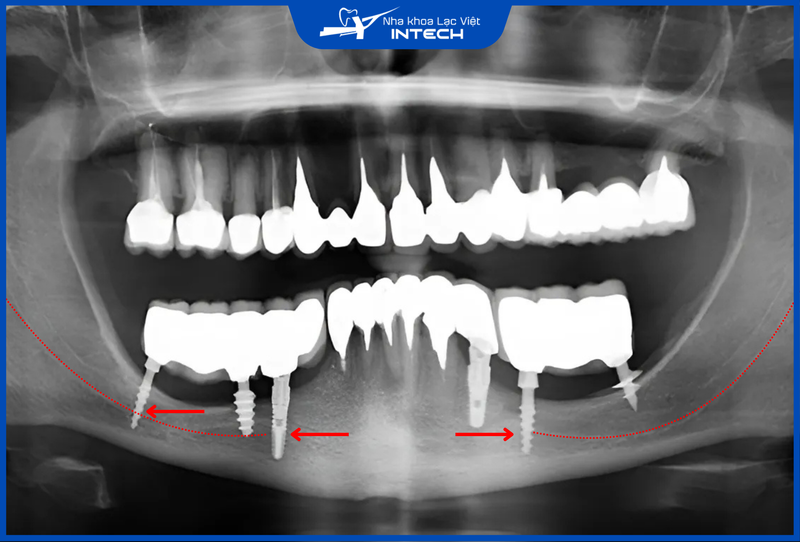

4.2. Trụ Implant tích hợp xương hàm kém

Trụ giá rẻ thường cho khả năng tích hợp kém vì được làm từ vật liệu “rởm” như Titanium chứa nhiều tạp chất, các hợp kim dễ gãy như chì, crom-coban... Bên cạnh đó, trụ giá rẻ chắc chắn không ứng dụng các công nghệ xử lý bề mặt hiện đại, vì thế không thể tạo ra bề mặt tương tự như xương người, từ đó làm kéo dài thời gian tích hợp hoặc thậm chí không thể tích hợp xương hàm.

Hậu quả có thể xảy ra là cắm Implant bị lung lay, trụ Implant bị nứt, gãy, vị trí cấy ghép bị viêm nhiễm, sưng đau, chảy máu hoặc mủ kéo dài, tiêu xương hàm, hoại tử vùng cấy ghép...

Trụ Implant rẻ tiền thường có nguy cơ mất tích hợp cao hơn, gây ra các biến chứng nghiêm trọng